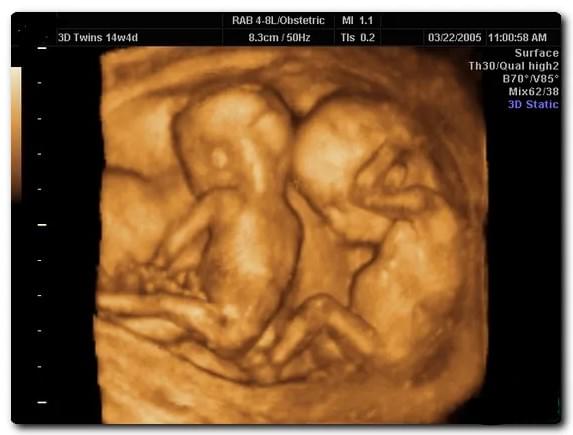

Наверняка определить количество плодов можно только по УЗИ. Исследование покажет также предлежание, размещение, тип и количество плацент и плодных мешков, объем амниотической жидкости, физическое состояние плодов и состояние кровотока в матке.

Из-за повышенной вероятности патологий УЗИ при многоплодной беременности делают чаще, чем при вынашивании одного ребенка. При монозиготной – каждые две недели, при двуяйцевой – 1 раз в месяц.